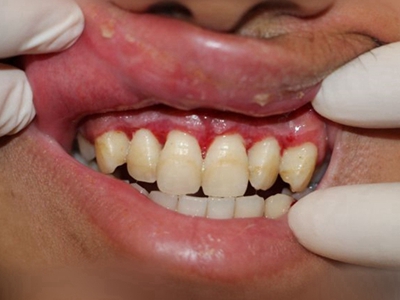

牙龈炎是发生于牙龈组织的炎症,患者可出现牙龈出血伴肿胀、发红、正常形态改变和偶尔不适等症状。本病主要由口腔卫生状况差导致,包括口腔不洁、牙菌斑等,诊断依据临床检查,治疗包括专业牙齿清洁和加强家庭口腔卫生。

牙龈炎可先引起牙齿与牙龈之间的沟(龈沟)加深,然后牙龈充血,炎症围绕一个或多个牙齿,伴牙龈乳头肿胀和易出血。一般无痛,可自行消退,也可维持轻度炎症数年。

牙龈炎常见的病因是口腔卫生差,不良的口腔卫生使牙菌斑沉积于牙齿与牙龈之间,造成龈沟加深,另外牙结石、不良修复体等也可造成牙龈炎的发生。